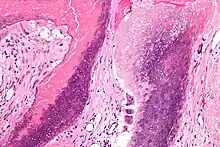

Microscopie : Pilomatrixome. HE, x24. Présence d'une tumeur calcifiée dans le derme profond.

Microscopie : Pilomatrixome. HE, X100. Présence de cellules "fantômes" partiellement calcifiées et de cellules géantes multinucléées à corps étrangers.